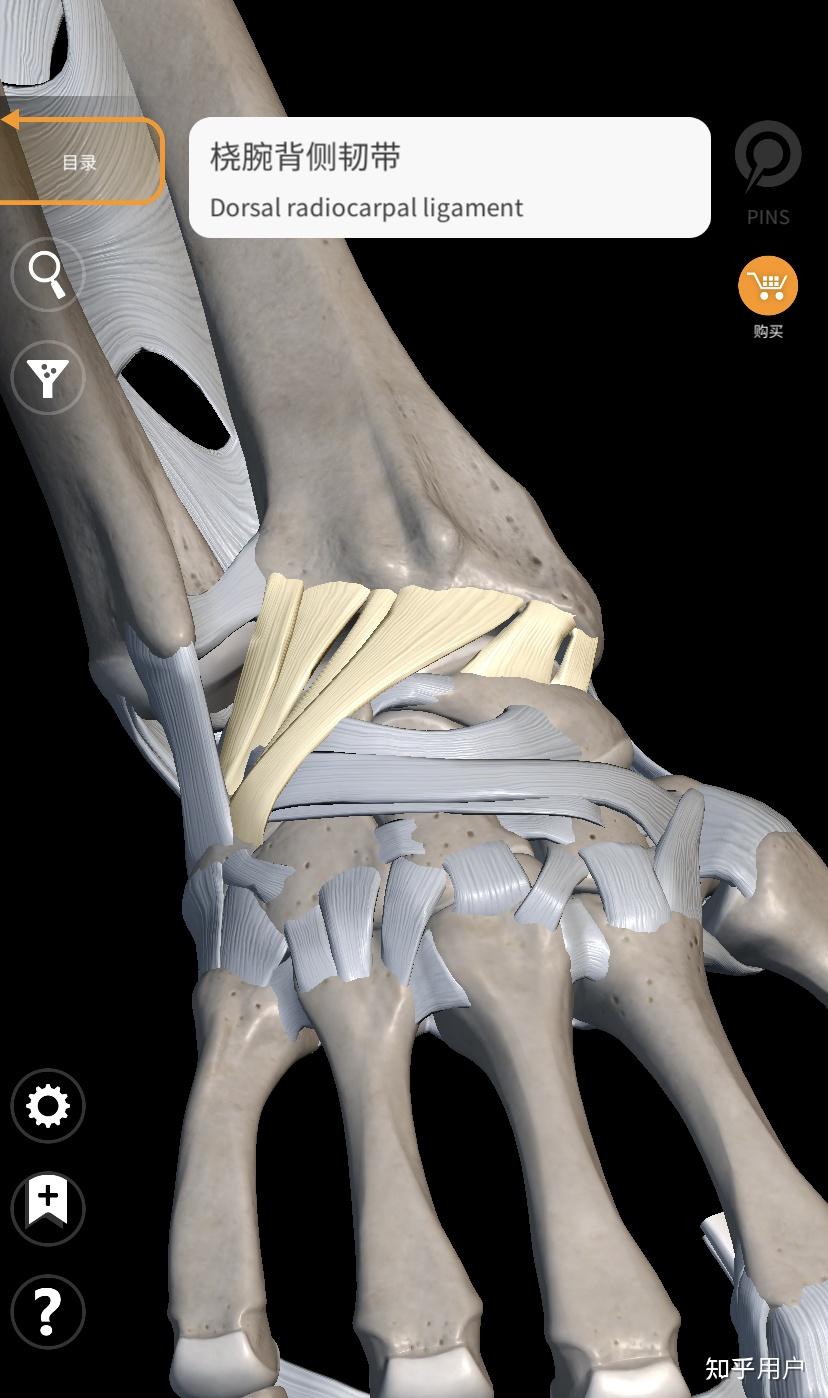

三角纤维软骨复合体周围的韧带

三角纤维软骨复合体核心是一个软骨盘,周围有一圈韧带,像一个吊床一样